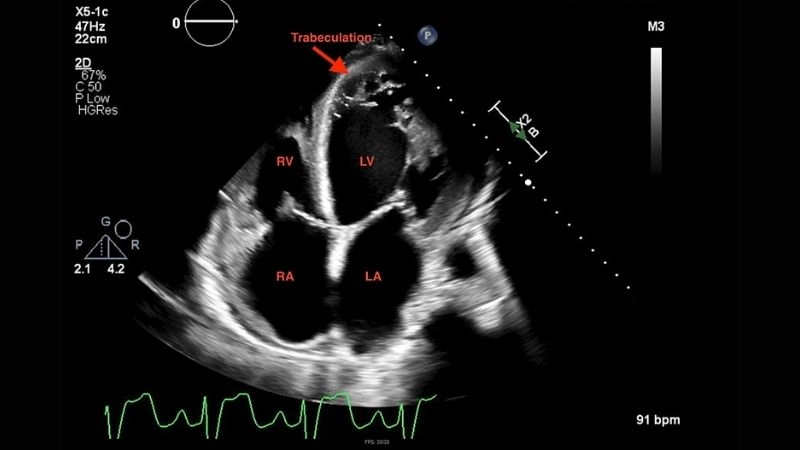

Images visual examples of Left Ventricular Non-compaction Cardiomyopathy

This abnormal structure weakens heart function, disrupts blood circulation, and can lead to life-threatening complications if not diagnosed early.